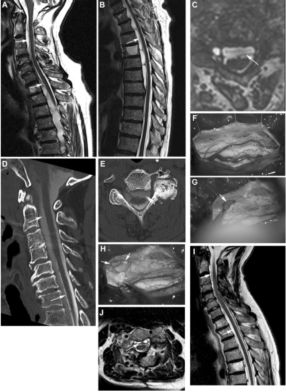

Ⅱ型:硬膜间夹层硬膜内层有缺损,CSF可以沿着内层硬膜的缺损进入两层硬膜之间,形成硬膜间夹层。夹层可以占据较长节段的椎管,引起占位效应;还可导致低颅压综合征和铁质沉积症,原因与脑脊液的缓慢流出及夹层囊肿壁的反复缓慢渗血相关。术前必须进行椎管造影后的CT扫描,确定硬膜缺损的部位(图3)。手术采用硬膜内入路,关键是关闭内层硬膜缺损,采用肌肉片直接缝合或与纤维蛋白胶粘合修补。

![]()

图3. 71岁男性患者,右侧无力逐渐加重4年。颈椎(A)和胸椎(B)MRI-T2加权矢状位显示,硬膜夹层范围在C2-T8;在T2-T7节段脊髓明显受压。C.C4水平MRI-T2加权轴位显示脊髓腹侧的硬膜夹层和C5神经根袖套病变。椎管造影后CT矢状位重建(D)及轴位扫描(E)显示硬膜夹层内造影剂填充,箭头指示硬膜的内层。F.C3-C5椎板切除后,切开硬膜,显露脊髓与硬膜之间粘连。G.分离粘连后,可见C5神经根袖套处的缺损。H.硬膜缺损用肌肉片和胶水给予修补。术后MRI-T2矢状位(I)和轴位(J)示夹层基本消失,脊髓受压明显改善。